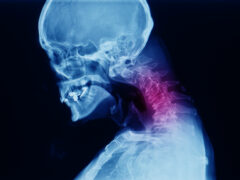

Lateral cervical spine x-ray showing spondylosis with kyphotic deformity of cervical spine. Chin to chest deformity. It cause neck pain, spondylotic myelopathy and radiculopathy.

Mielopatía cervical espondilótica

¿Qué es la mielopatía cervical espondilótica (MCE)? Su médula espinal es un grupo de nervios que se extiende desde su cabeza hasta su espalda baja. La columna cervical es la parte del cuello. La mi...